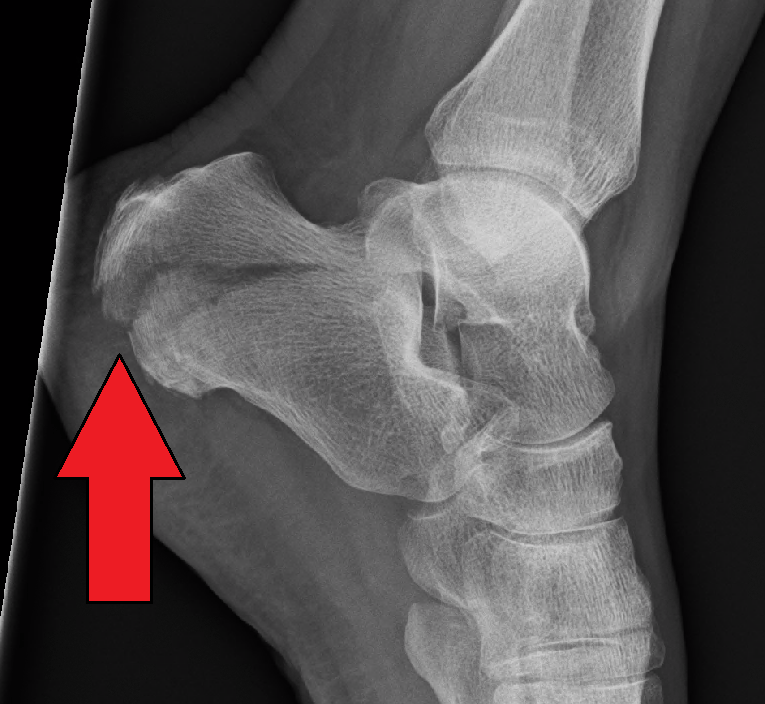

Immediate swelling, pain, and inability to bear weight on the heel. Minimal deformity unless comminuted fracture occurs. Two words in the name.

Calcaneus Fracture